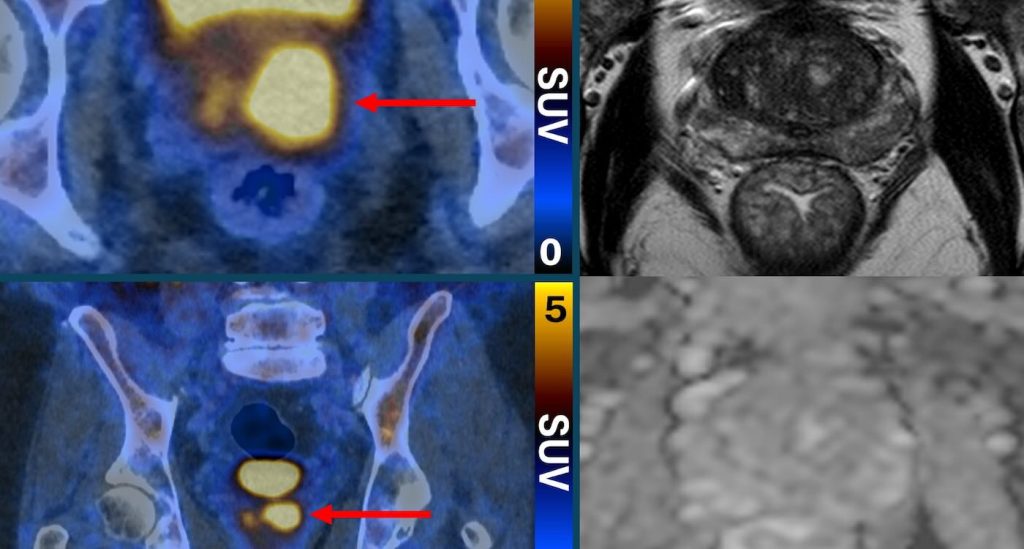

Prostat Kanserini “Parlatan” Yeni Tarama Yöntemi Ağrısız Tanıda Çığır Açıyor Bilim insanları, prostat kanseri hücrelerini adeta “parlatan” yenilikçi bir görüntüleme